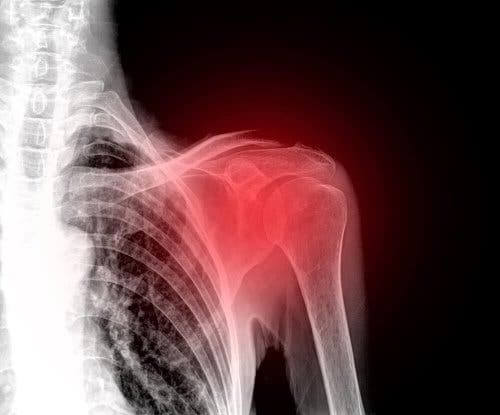

En ruptur i rotatorcuffen är en skada i axeln som ofta drabbar människor i medelåldern. Det är idag en av de främsta orsakerna till axelvärk.

Symtomen som uppstår beror på svårighetsgraden av skadan. Det dominerande symtomet är dock smärta i axeln. Alla axelledsrörelser blir på så sätt begränsade.

En läkare måste först undersöka axeln för att kunna diagnostisera rotatorcuffruptur. Läkaren kommer att fokusera på förmågan att röra axelleden, styrkan i axeln, och eventuell ledvärk. Undersökningen kommer säkerligen också innehålla komplementära tester som till exempel ultraljud eller magnetisk resonanstomografi. Med ett ultraljud kan man nämligen utvärdera hur senor och muskler fungerar i rörelse. De är dessutom både prisvärda och icke-invasiva alternativ.